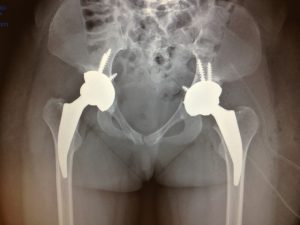

Prótesis de cadera

Reemplaza parcial o totalmente la articulación de la cadera, aliviando el dolor y restaurando la movilidad en casos de artrosis, fracturas o necrosis femoral.